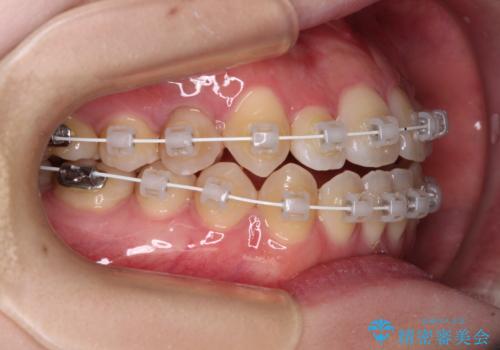

- 審美装置

- 1年6ヶ月

- 10-30回

ワイヤー矯正での開咬改善には時間がかかります。

舌の突出癖改善のトレーニングをしっかりと行っていただき、上下前歯が接触する咬み合わせを達成することができました。